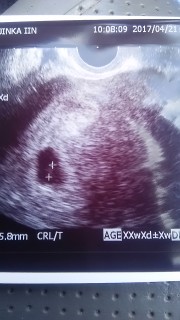

ずっと胎嚢しか見えてなくて今回も見えなかったら?と不安で一杯でしたが無事写ってくれて、心臓の動きも確認とれました。5.8と小さめみたいですが逢えました。